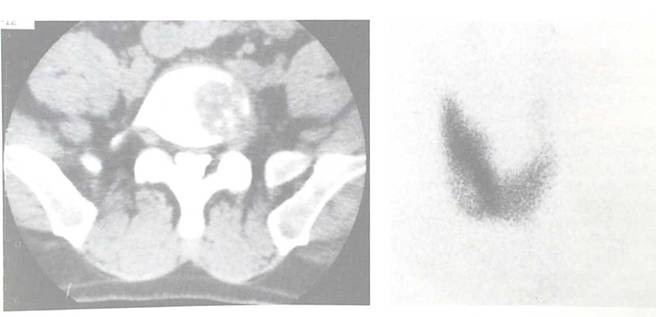

病例四:肺癌,全身骨转移

男性,82岁(全身显像可见多发骨代谢异常增高影):颅骨、全脊柱、肋骨、股骨多发性骨转移瘤。